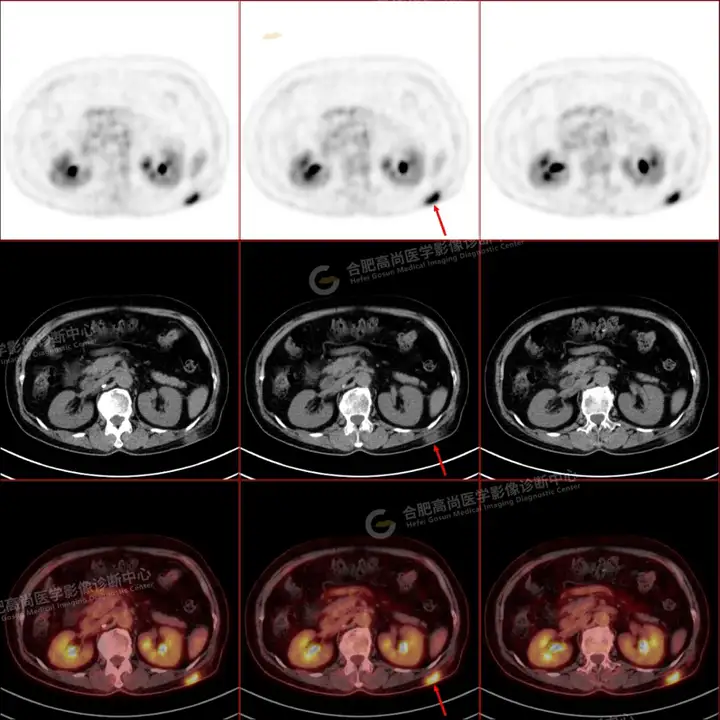

PETCT检查所示:图1、3-17全身多处(双上臂、胸背部、左侧乳腺、左侧腰部、腹壁、双侧臀部及双侧大腿)皮肤下结节及肿块样软组织密度灶,FDG代谢不同程度增高,双侧颈部、左侧锁骨区、纵隔内(1区)及双侧腋窝多发肿大淋巴结,FDG代谢明显增高,符合皮肤来源淋巴瘤。